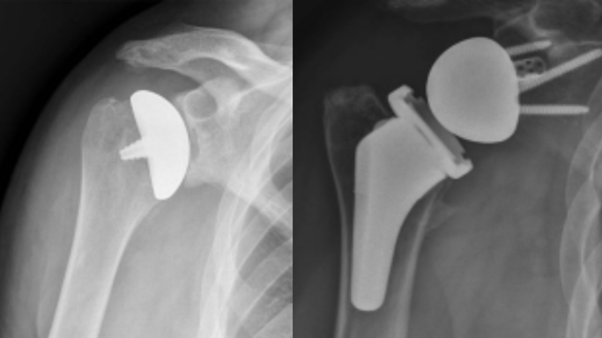

Reverse Total Shoulder Replacement (RTSA) is a specialised surgical procedure designed to treat shoulder arthritis, rotator cuff tears, and severe joint damage that cannot be effectively addressed with conventional shoulder replacement methods. This innovative surgery reverses the natural mechanics of the shoulder joint, allowing the deltoid muscle to take over the function of the damaged rotator cuff, improving shoulder function and alleviating pain.

Reverse Total Shoulder Replacement involves switching the normal ball-and-socket mechanics of the shoulder joint. The ball (humeral head) is removed and replaced with a socket, while the socket (glenoid) in the shoulder blade is replaced with a ball-shaped prosthesis. This reversal allows the deltoid muscle to perform movements that are usually controlled by the rotator cuff, particularly in cases of irreparable rotator cuff tears.

- The humerus is fitted with a socket-shaped component that allows it to accommodate the ball-shaped component placed in the glenoid.

- The glenoid is fitted with a ball-shaped prosthesis, allowing the deltoid muscle to lift the arm and compensate for the damaged rotator cuff.